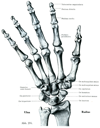

手の骨

手の関節